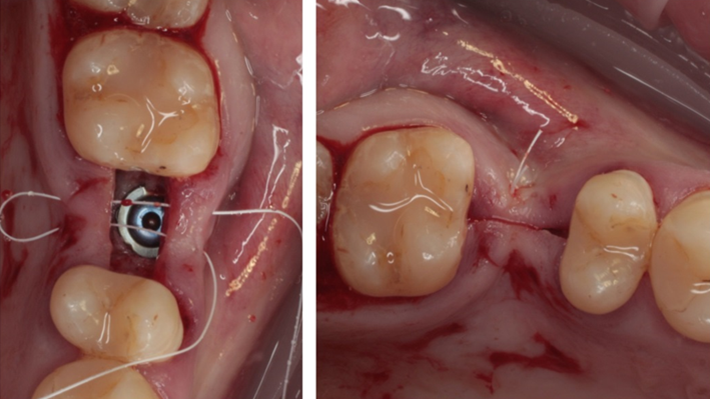

Clinical case: # 46 implant placement & GBR using i-Gen membrane for significant vertical resorption & mixed bone defect

- Courtesy of Dr. Iulian Filipov, Romania -

AnyRidge, mandibular posterior, i-Gen, resorption, bone defect, bone regeneration, space management, #46, GBR, Dr. Iulian Filipov

AnyRidge implant system, i-Gen

“AnyRidge KnifeThread achieves excellent stability in regenerated bone & even in only 3mm bone height!”